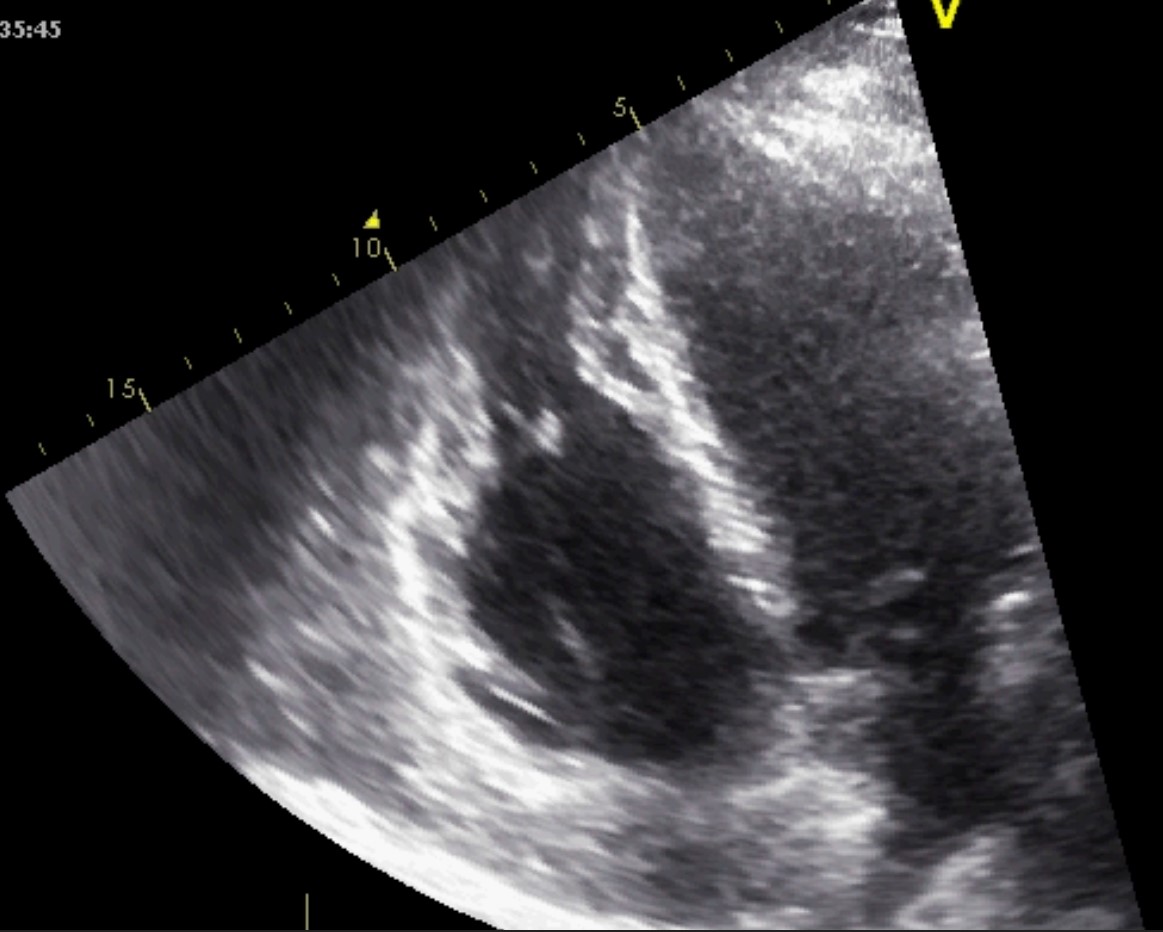

The initial imaging evaluation comprises of two main 2D echocardiography parameters: left ventricle ejection fraction (LVEF) less than 40% or fractional shortening less than 25% [6]. However, the comprehensive diagnosis of DCM should consider aspects of the clinical presentation, patient examination and other test results. Dilatation of the LV, especially end-diastolic and end-systolic transverse diameter enlargement (spherical remodeling), associated with reduced wall thickness, is easily recognized with 2D echocardiography in parasternal long-axis view (See Fig. 1 and Appendix Video 1).

Fig. 1.Echocardiographic aspect of DCM. Parasternal long-axis view showing a dilated left atrium and left ventricle in diastole. An online video of this patient with idiopathic dilated cardiomyopathy is available (Appendix Video 1).